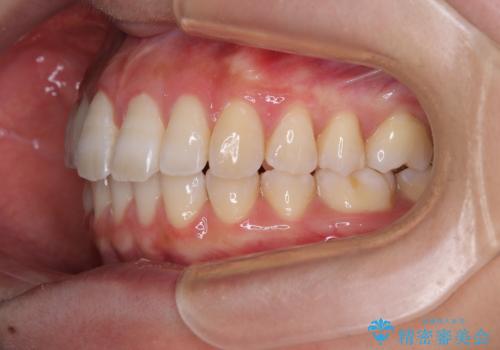

1年弱で治療方針を変更したため、治療期間は長くなりましたが、スペースは無事に閉じ、咬合の違和感なく仕上げることができました。

ただし、両方の臼歯部は理想的な咬合とは言えないため、咬合による歯の外傷を防ぐため、就寝時にはマウスピースを継続使用するようお願いしております。